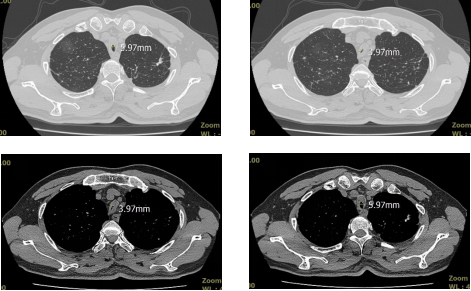

入院时患者胸部CT:气管有相邻两段狭窄,最窄处仅有不到4mm宽(图1)。

图1 入院时胸部CT示气管明显狭窄